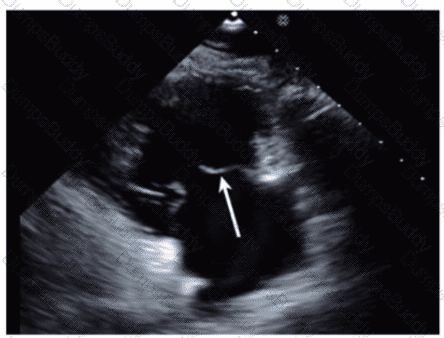

Which left ventricular regional wall segment is indicated by the arrow on this image?